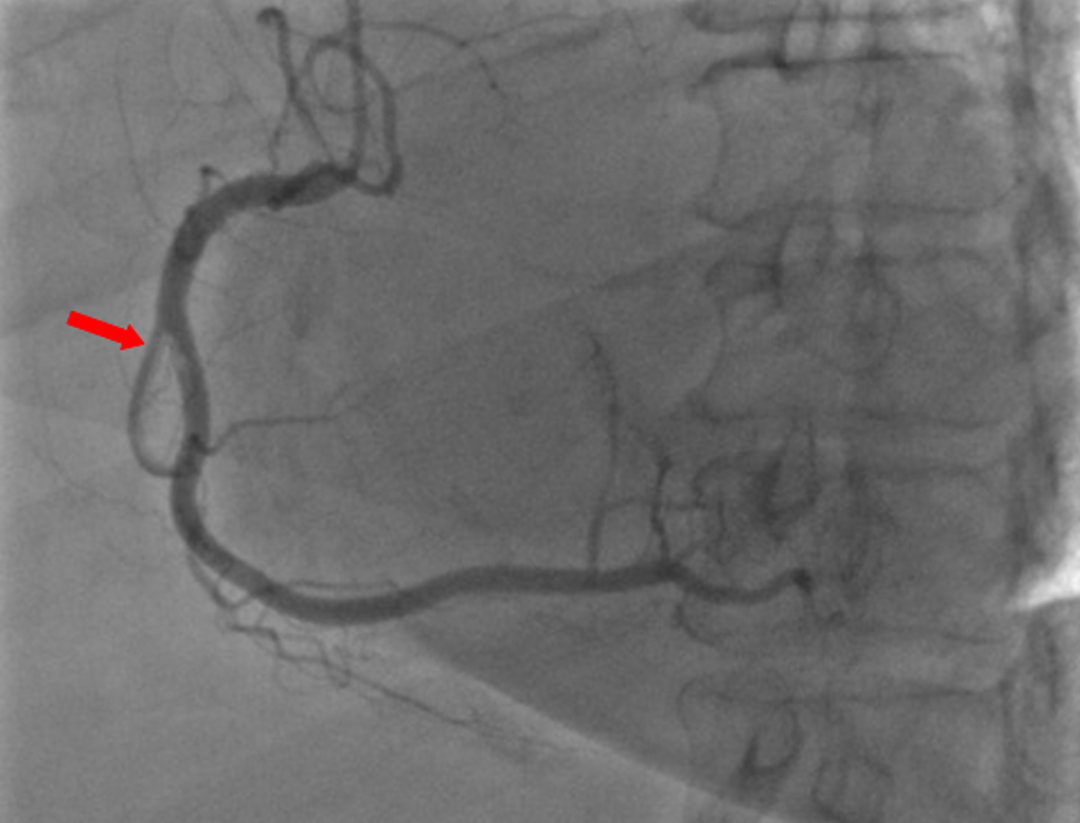

模糊病变陷阱难料?

预规划助力,应对模糊病变游刃有余

迂曲钙化病变